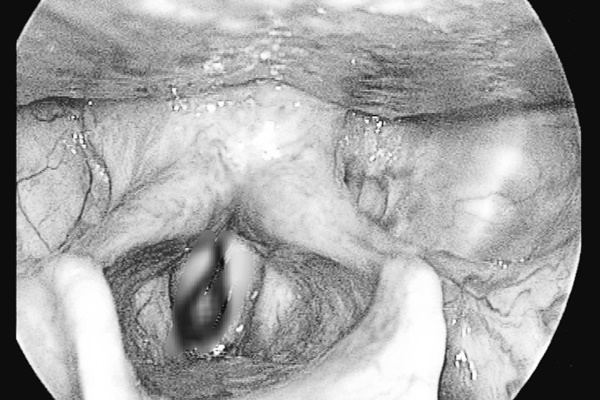

Con đỉa trong mũi bệnh nhân. |

Qua nội soi, bác sĩ xác định có dị vật bên trong hốc mũi bệnh nhân là một con đỉa có kích thước khoảng 4cm, to bằng đầu đũa. Bệnh nhân được chỉ định gắp dị vật ra ngoài, rửa mũi và sát khuẩn.